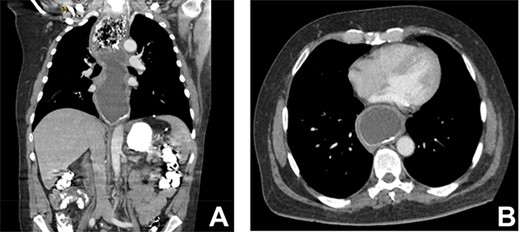

As part of the assessment, computed tomography (CT) coronary angiogram study was performed and it demonstrated a large fluid-filled oesophagus causing partial compression of the left atrium. Barium swallow (Fig. 1A and B), CT chest and abdomen (Fig. 2A and B) and transthoracic echocardiography (TTE) showed a 7.1-cm dilated oesophagus causing left atrial compression and a small hiatal hernia (Fig. 3).

(A) CT coronal image of chest and abdomen demonstrating megaoesophagus secondary to the LAGB; (B) CT axial image of chest demonstrating megaoesophagus causing left atrial compression.